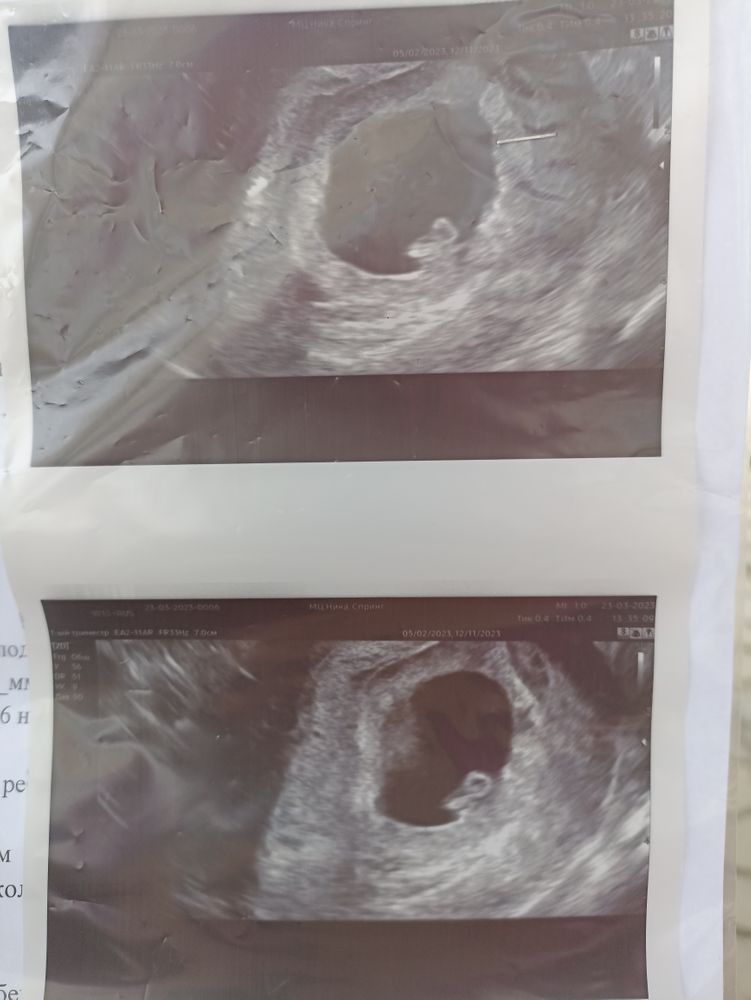

Первые фото😍

Красота😍 У меня в 9 неделек уже и ручки и ножки видно, конечно же ещё в этапе роста, но всё же)

Юлия, Ну головка уже явно есть) А тельце растёт)

У вас прям ребенок виден,у меня в 8 недель,желточный мешок и как пятнышко рядом,непонятно вообще, что ребенок,а у вас прям видно

Первое узи, и возможно двойное счастье ЧСС плода 10+1